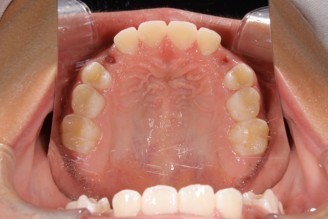

04:深い噛み合わせとガタガタの歯並び

矯正治療の症例写真

矯正治療終了後の症例写真

保定期間の写真

症例・治療内容について

• 主訴:上の歯と下の歯が逆に噛んでいるところがある

• 診断あるいは主な症状:交叉咬合

• 年齢:29歳(治療開始年齢)

• 治療に用いた主な装置:マルチブラケットによる歯列矯正

• 抜歯部位:なし

• 治療期間:2年1ヶ月

• 通院回数:25回(矯正治療を目的とした来院)

• 治療費概算:550,000円(税込)